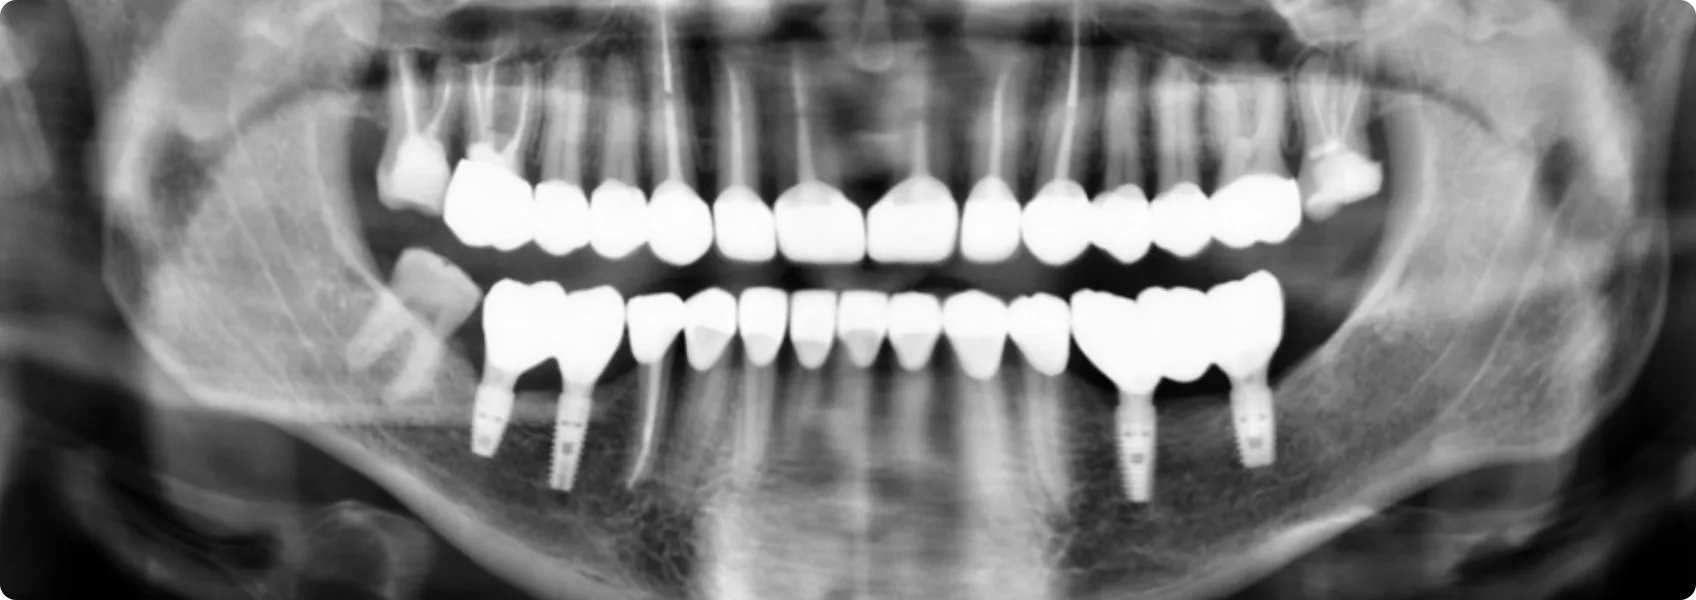

Najpierw dokładnie przeanalizowaliśmy i przygotowaliśmy fundamenty pod rekonstukcję. Zaczęliśmy od diagnostyki i analizy zdjęć RTG.

RTG pozwala zajrzeć „pod powierzchnię” – zobaczyć korzenie zębów, kość wyrostka zębodołowego, stan tkanek wokół korzeni, a także wewnętrzną budowę zębów (np. komorę miazgi, kanały korzeniowe).

Dzięki RTG możemy znaleźć stany zapalne, niewidoczne gołym okiem. Bez niego nie mielibyśmy jak wykryć problemów, które mogłyby prowadzić do poważnych powikłań.

RTG pokazało, że filary zębów własnych Pacjenta — te, na których miała opierać się przyszła rekonstrukcja — były zbyt krótkie.

Filary zębów to naturalne zęby, które po odpowiednim przygotowaniu (najczęściej oszlifowaniu) posłużą jako podpora dla stałych uzupełnień protetycznych. Zbyt krótkie zęby to poważne wyzwanie i ryzyko dla przyszłej odbudowy. Takie filary nie dają gwarancji, że korony czy mosty będą stabilnie i trwale osadzone.

Wyleczyliśmy zęby. Nadszedł czas na zaplanowanie implantów w miejscu braku zębów.

Implantacją zajął się nasz chirurg szczękowo-twarzowy dr n. med. Piotr Chomik. Wstępne zdjęcia RTG pozwoliły mu ogólnie ocenić sytuację i przybliżoną wysokość kości. Do precyzyjnego i bezpiecznego zaplanowania implantacji potrzebował jednak dodatkowej tomografii komputerowej (CBCT).

W dolnym łuku zębowym doktor Piotr wszczepił łącznie cztery implanty.

Tak zaplanowany zabieg chirurgiczny przebiegł bez przeszkód, a wszystkie implanty na finalnym zdjęciu RTG wyglądają na stabilne i jakby radosne. :-)